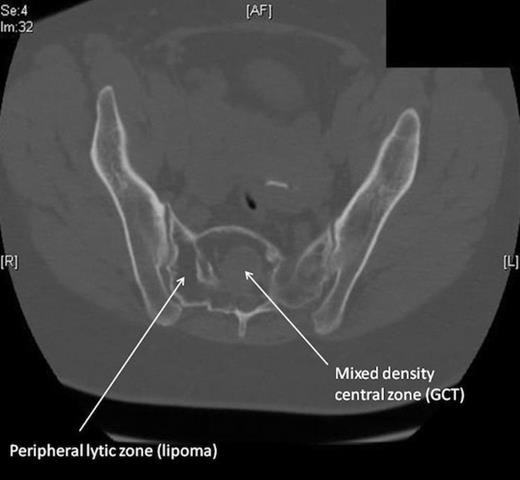

Blood tests including full blood count, urea & electrolytes and inflammatory markers were normal. The patient underwent plain radiographs, MRI and CT scans of the lumbar spine and pelvis. Plain radiographs of the spine and pelvis were normal. The MRI scan (fig. 1) revealed a heterogeneous mass within the proximal sacrum (high signal on T2-weighting), occupying the midline and extending to the sacral ala on the right side, measuring approximately 5x6 cm. Within this lesion was a 3cm area of abnormal low signal towards the midline of the sacrum. The lesion was in close proximity to the exiting right S1 and S2 nerve roots. The CT scan of the pelvis (fig. 2) confirmed the presence of a lytic lesion in the sacrum containing a smaller focus of different signal intensity.

A percutaneous biopsy was performed which revealed the presence of adipose cells in the periphery of the mass. The central portion showed polygonal multinuclear tumour cells with mild atypia consistent with a giant cell tumour. The peripheral tissue was confirmed as adipose in nature. The management of our patient consisted of surgical excision from a posterior approach. The thecal sac and exiting L5, S1 and S2 nerve roots were identified and protected (fig 3). The peripheral fatty tissue was removed using an ultrasonic surgical aspirator, exposing the central GCT mass. This was carefully dissected free and removed en-bloc. The cavity left behind was filled with frozen femoral head allograft.

This 58 year old female presented with acute-on-chronic low back pain with features of neurological compromise. Our patient’s presentation of diffuse low back pain with radiation to the lower limb is typical of degenerate disc disease but could also be seen in a sacral GCT. MRI revealed a mass within the sacrum consisting of two distinct parts: a peripheral high-signal area and a central low-signal area. The high intensity signal (on T2-weighting) was characteristic of fatty tissue. Radiographically, the central area was in keeping with a giant cell tumour (GCT), although typically these tend to occur eccentrically rather than in the midline. GCTs are low signal intensity on T1 and T2-weighted images, relating to the haemorrhagic and fibrotic components of the tumour (1). Histology revealed multinucleated cells, characteristic of the giant cells (resembling osteoclasts) that are pathognomic of GCT.